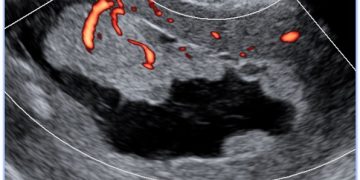

How To Do Settembre 2022: corretto settaggio del Doppler in ostetricia

Cari soci, questo mese un nuovo video "How to do", sul corretto settaggio del Doppler in Ostetricia. Grazie a Paola Quaresima! Il video è accessibile ai soli soci SIEOG attraverso...